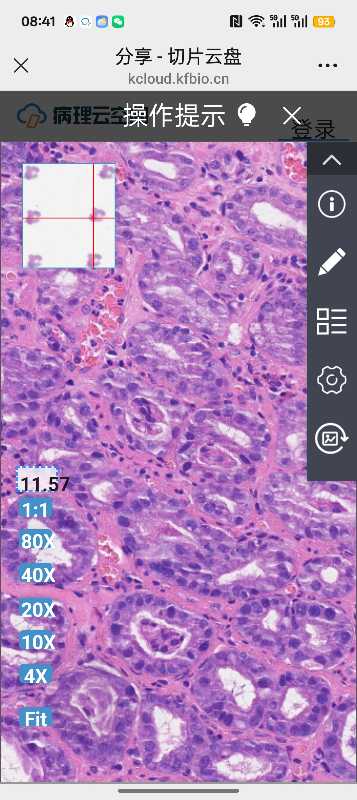

胃活检

性别

女

年龄

52

临床诊断

粘膜隆起

一般病史

胃部不适

标本名称

大体所见

软组织1块

内镜示:胃体大弯侧见0.5*0.5cm粘膜隆起,表面糜烂,发红。老师们帮忙看看怎发报告

送检粘膜呈慢性炎伴表浅糜烂